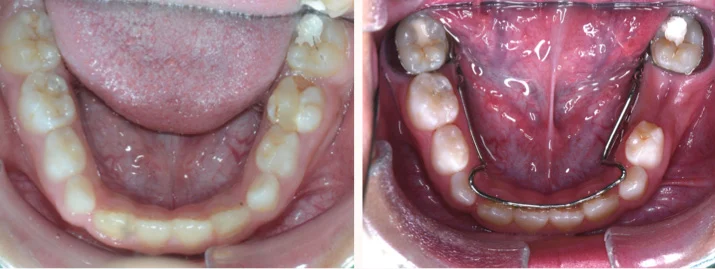

雙側維持器

當乳牙蛀牙太嚴重,有牙根或是齒槽骨的吸收時, 為了避免感染的乳牙影響到恆牙發育,會提早將乳牙拔除! 空間維持器的目的在於保留過早拔除的乳牙的空間, 若沒有給予適當的空間維持器,可能會影響底下恆牙萌發,導致齒列紊亂!